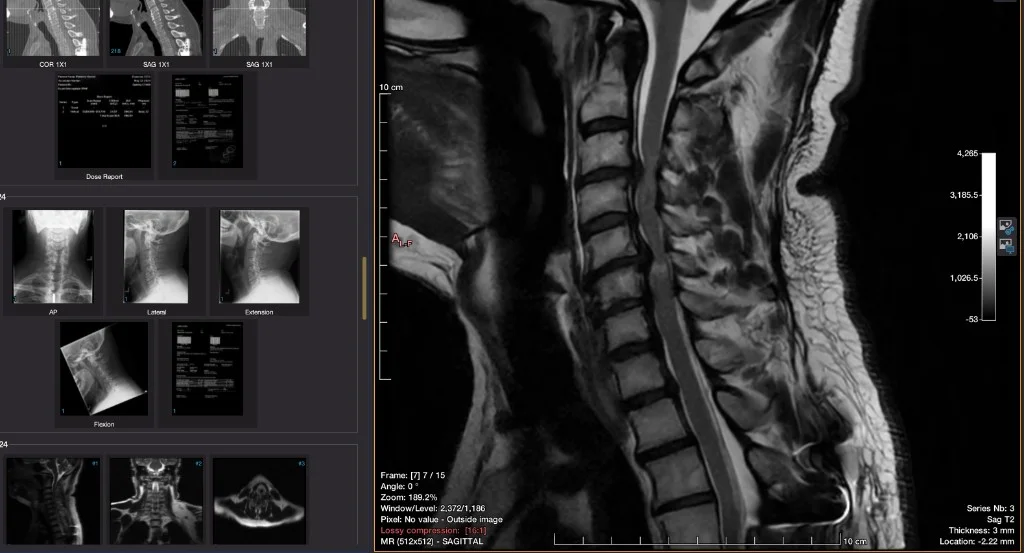

Cervical spine MRI in a viewer with sagittal neck image enlarged and series thumbnails visible

This one made it click for me: these are not just pictures, this is actual data.